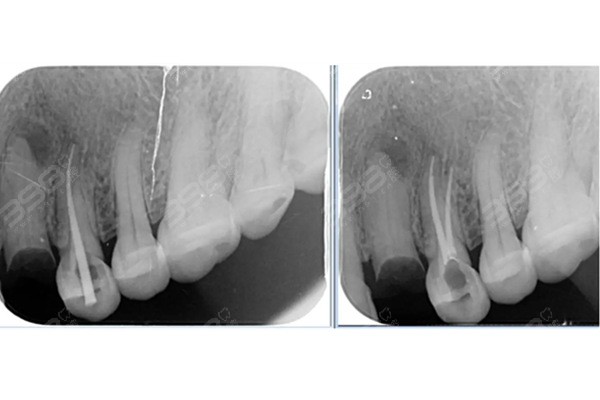

根管治療是一種通過清除牙齒內(nèi)部感染物質(zhì),對牙齒進(jìn)行修復(fù)和恢復(fù)的方法,這種方法適用于牙髓炎、根尖周炎等牙齒疾病的治療,根管治療的主要目的是消除感染、防止再次感染,并恢復(fù)牙齒的正常功能。